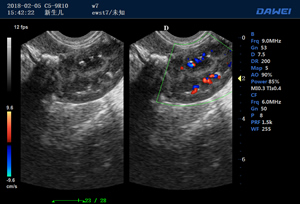

S80高端便攜獸用彩超-彩色多普勒多普勒超聲診斷儀掃描圖 S80高端便攜獸用彩超-彩色多普勒多普勒超聲診斷儀 S80高端便攜獸用彩超-彩色多普勒多普勒超聲診斷儀